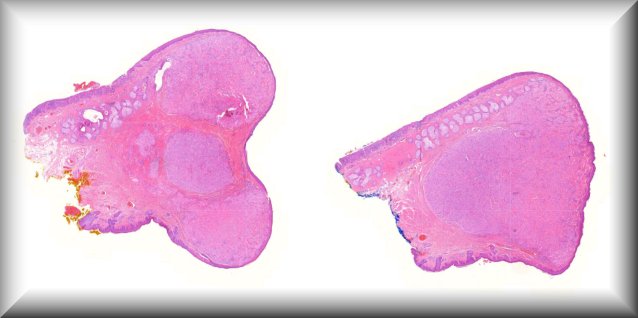

María Antonia Saornil (Valladolid): 19-year-old male patient who, in the last 3 months, had a progressive and extensive protrusion in the temporal sclera of the left eye. The patient also reports noticing loss of nasal visual field. |